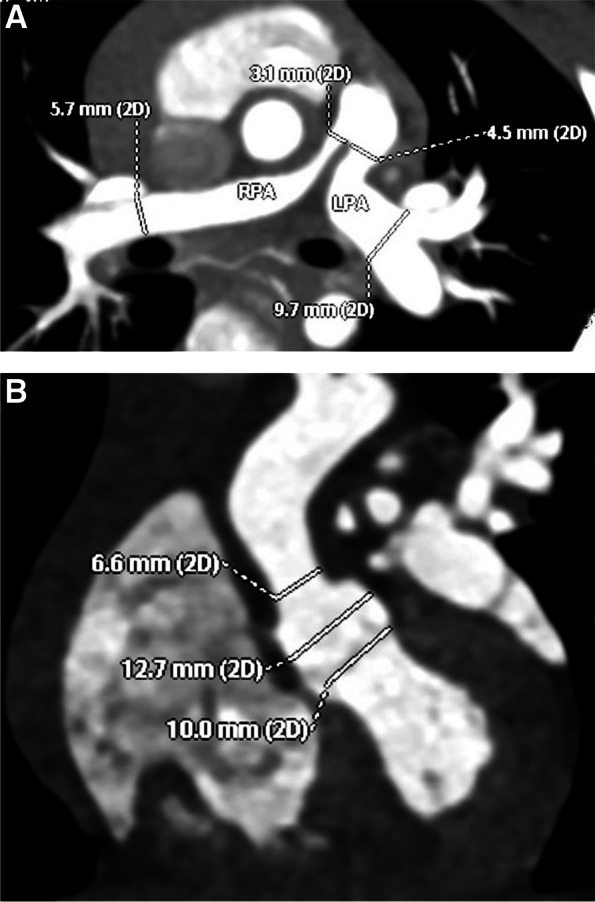

Echocardiographic examination was performed after admission to the hospital, which showed severe pulmonary artery stenosis (pressure gradients (PG) between the right ventricle and pulmonary artery = 75mmHg), and the thickening and stenosis of the aortic wall at the sinotubular junction (diameter = 6.8 mm, normal range 9 ~ 13.5 mm). Cardiac computed tomographic angiography (CCTA) showed the proximal branch of pulmonary artery stenosis (shown in Fig. 1A), and the stenosis of the aorta at the sinotubular junction (shown in Fig. 1B). Cardiac catheterization was performed and indicated mild sinotubular junction stenosis with a pressure gradient of 15mmHg (shown in Fig. 2A), the branch pulmonary artery stenosis (PG = 84mmHg) (shown in Fig. 2B).

Fig. 1.

CCTA showed the proximal branch of pulmonary artery stenosis and the aortic wall at the sinotubular junction. A The diameter of the main pulmonary artery was 7.1 mm, the diameter of the proximal left pulmonary artery (LPA) was 4.5 mm, the distal bifurcation of the LPA was 9.7 mm, and the proximal right pulmonary artery (RPA) was 3.1 mm, and the distal RPA was 5.7 mm. B The diameter of the sinotubular junction was 6.6 mm, the diameter of the aortic annulus was 10 mm, and the diameter of the aortic sinus was 12.7 mm